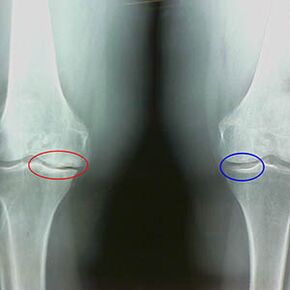

Skoré X -ray vlastnosti druhej fázy artrózy kolena:

- špicaté okraje hľúz na predpis na holennej kosti, kde je pripojený krížový väz;

- zúženie kĺbovej medzery na strednej strane;

- Špicaté okraje kondylov kostí na stredných stranách, menej často v laterálnom - v závislosti od vývoja deformácie valgus alebo variorového kĺbu.

Pre druhú fázu v Larsene Charakteristické je zúženie kĺbovej medzery o viac ako 50%, ale to sa dá skontrolovať iba v dynamike alebo porovnaní s odlišným kĺbom.